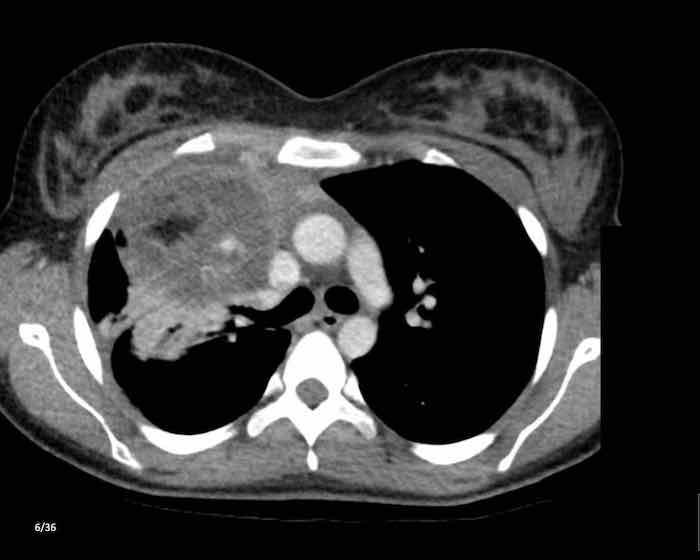

Các hình ảnh này của một nam giới 71 tuổi.

Trên CT ngực, tình cờ phát hiện một khối ở tuyến ức.

Hãy phân tích các hình ảnh. Nhận định của bạn là gì?

Hình ảnh

Một phần tổn thương có ngấm thuốc cản quang và có một số vôi hóa, có thể nằm ở thành nang.

Khi một tổn thương tuyến ức có thành phần đặc, nguyên tắc là… “khi còn nghi ngờ, hãy phẫu thuật cắt bỏ”.

Tổn thương đã được phẫu thuật cắt bỏ dựa trên kết quả CT và kết quả giải phẫu bệnh cho thấy đây là u tuyến ức dạng nang.